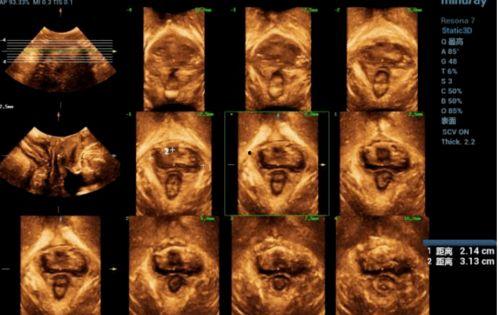

这时候,神奇的事情发生了!医生会通过屏幕上的视频,向你展示你的盆腔内部结构。哇,是不是觉得有点不可思议?其实,这些视频就像是一幅幅精美的画卷,让你可以直观地看到自己的盆腔内部。

盆底超声检查视频不仅仅是一幅幅美丽的画卷,它更是医生诊断妇科疾病的利器。通过观察视频,医生可以判断你的子宫、卵巢、输卵管等器官是否正常,是否存在囊肿、肌瘤等异常情况。

1. 子宫形态:正常的子宫呈倒置的梨形,如果子宫形态异常,可能意味着存在妇科疾病。

2. 卵巢大小:正常的卵巢大小约为4-5厘米,如果卵巢过大,可能存在囊肿等问题。

3. 输卵管通畅度:正常的输卵管应该是通畅的,如果输卵管不通,可能导致不孕。

4. 盆腔积液:盆腔积液可能是炎症、肿瘤等疾病的信号。